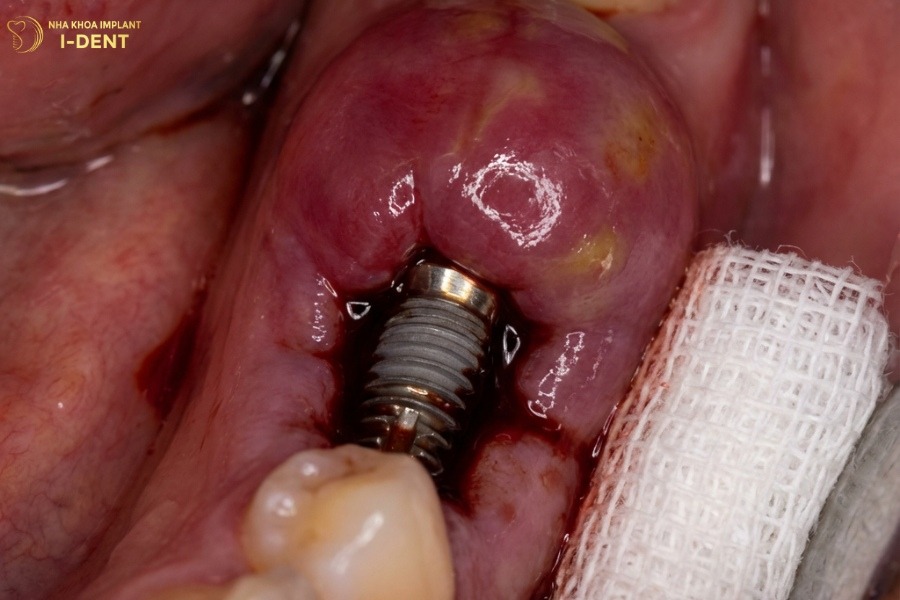

Nhiễm trùng vùng cấy implant

Hậu quả của việc cắm trụ implant thường gặp nhất là nhiễm trùng tại vị trí cấy ghép implant với nguy cơ 2-5% các ca cấy ghép. Nguyên nhân chính bao gồm vệ sinh răng miệng kém sau phẫu thuật, vi khuẩn từ viêm nha chu trước đó chưa được điều trị triệt để, hoặc môi trường phẫu thuật không đảm bảo vô trùng.

Biểu hiện của nhiễm trùng gồm sưng đau tăng dần, đỏ nóng vùng cấy ghép, có mủ hoặc dịch tiết, mùi hôi từ vùng implant và có thể kèm sốt. Nếu không được điều trị kịp thời, nhiễm trùng có thể lan rộng gây tiêu xương hàm, thất bại implant hoàn toàn, implant đào thải hoặc nhiễm trùng máu.

Nhiễm trùng vùng cấy ghép implant thường có biểu hiện xưng đỏ hoặc có dịch mủ tại vị trí cấy implant.